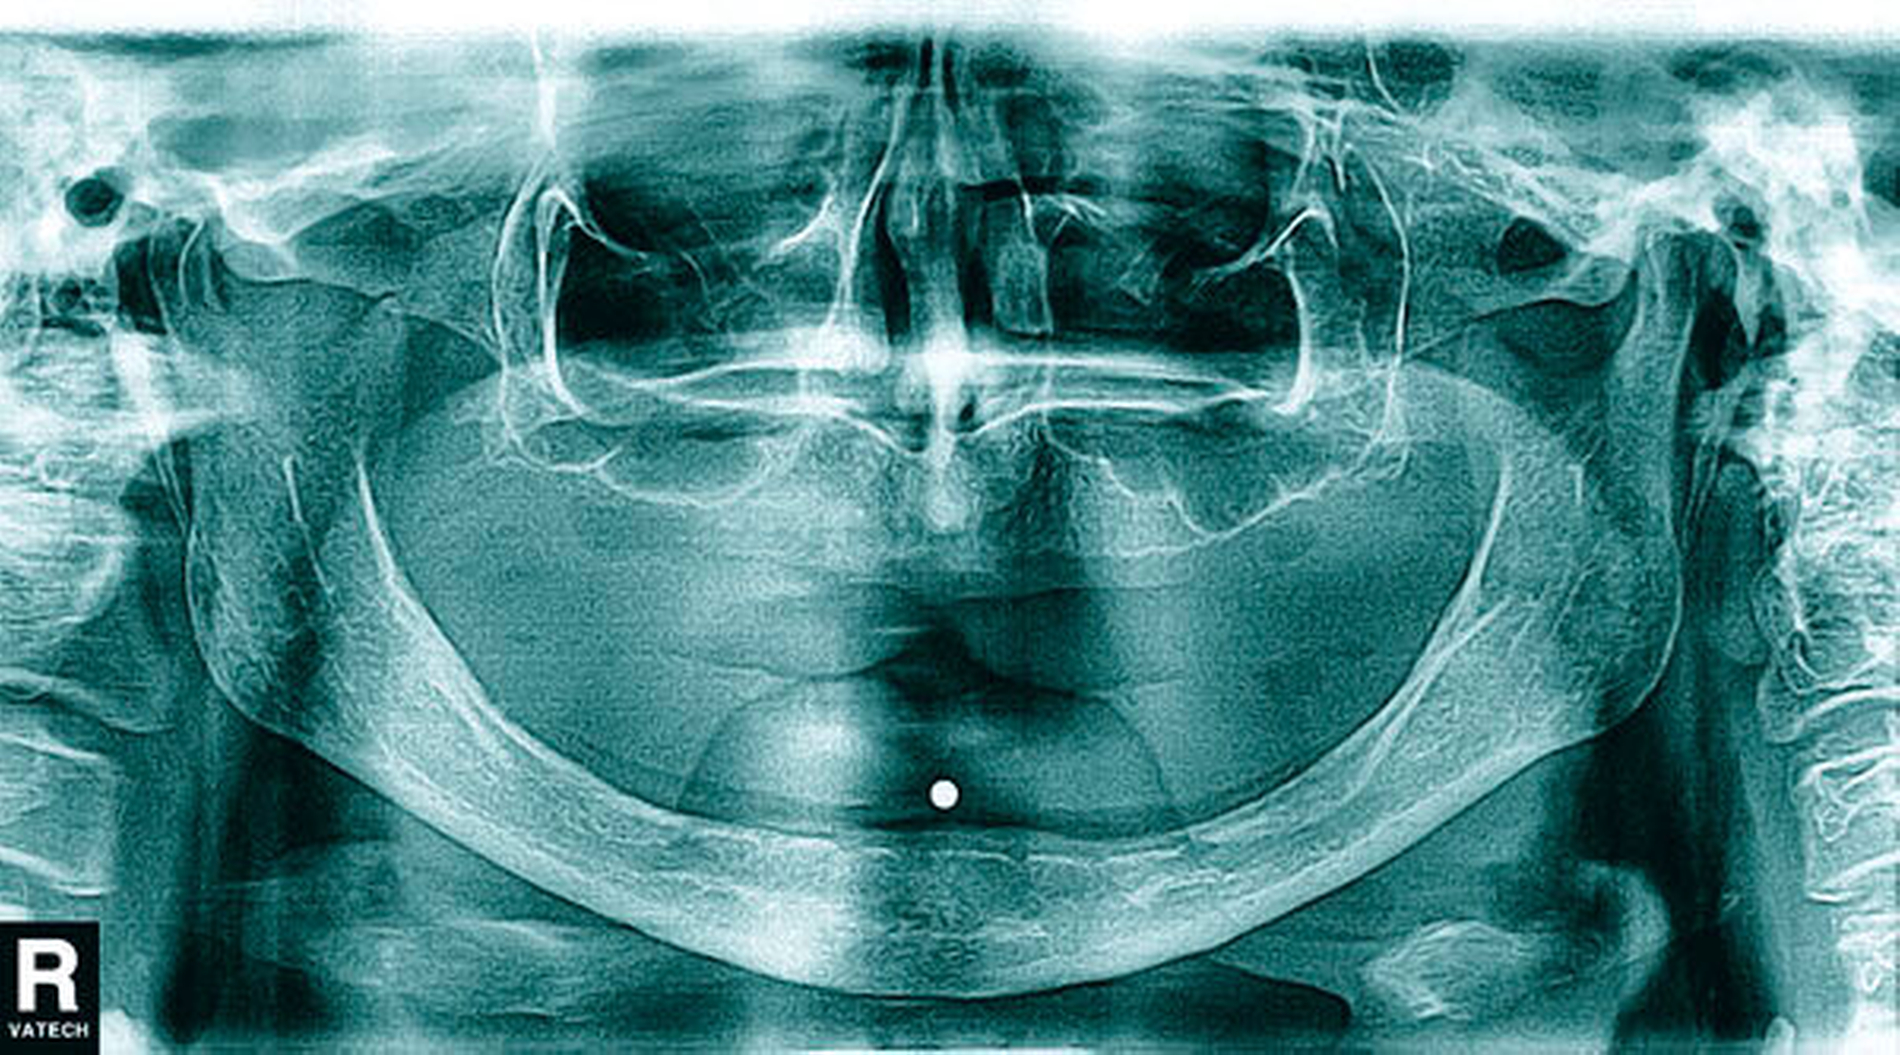

Untersucht wurden im Rahmen der Studie insgesamt 158 Patienten. Randomisiert wurden die Studienteilnehmer entweder der Gruppe mit Sofortbelastung des Implantats (n = 81) oder der Gruppe mit verzögerter Belastung nach drei Monaten Einheilungszeit (n = 77) zugeordnet. Voraussetzungen zur Teilnahme an der Studie waren (unter anderem) eine ausreichende Knochenhöhe von 11 bis 20 mm, keine Kontraindikationen für Implantate, ein Knochenlager, das keiner Augmentation bedarf, eine vorhandene, suffiziente Totalprothese im Ober- sowie im Unterkiefer mit bilateral balancierter Okklusion, die seit mindestens drei Monaten in situ ist, aber einen mangelhaften Halt im Unterkiefer aufweist. Für die präoperative Bildgebung wurde mithilfe einer Röntgenmesskugel, adjustiert an der Unterkieferprothese mit einem Durchmesser von 4 mm, eine Panoramaschichtaufnahme erstellt und das Knochenlager entsprechend für das Setzen eines enossalen Implantats (Camlog Screw Line, Camolg Biotechnologies, Wimsheim, Länge 13 mm, Durchmessser 3,8 mm) beurteilt (Abbildungen 1 und 2). Die Implantation folgte dem üblichen Vorgehen mit den zugehörigen Bohrern des Camlogsystems. Die Primärstabilität des Implantats wurde anhand des Osstell-Geräts (Osstell, Grothenburg, Schweden) beurteilt.

Anschließend sollte eine röntgenologische Kontrolle mittels Panoramaschichtaufnahme erfolgen. Nach einer Implantateinheilung von drei Monaten können chairside die Retentionselemente in den vorhandenen Zahnersatz eingearbeitet werden. Das Kugelkopfattachment (Gingivahöhe 1,5 mm, Camlog) wird mit einem manuellen Drehmomentschlüssel (Camlog) mit einem definierten Drehmoment von 30 Ncm eingesetzt (Abbildung 3).